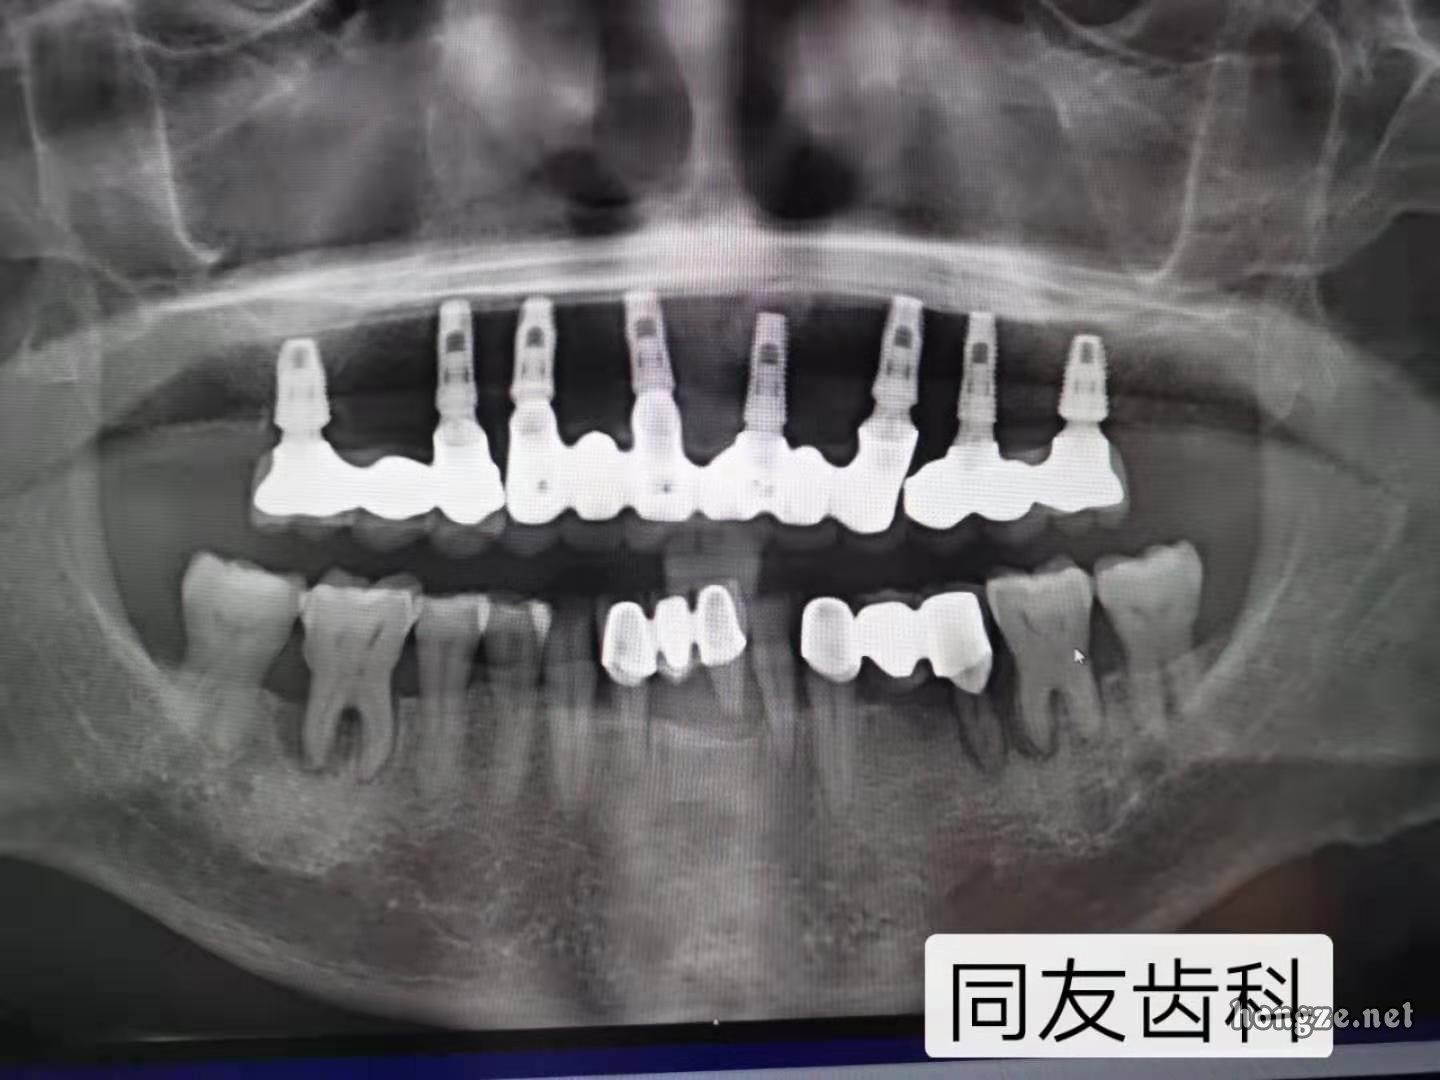

科普丨种植牙目前最久用了51年

目前,种植牙最长使用寿命的世界纪录由瑞典人Sven Johansson保持,已使用40余年。他是瑞典一位出租车老板兼司机。40多岁时,他所有的牙齿因病拔除,使用全口活动假牙。1967年,他接受了种植牙手术,成为世界上第二位安装纯钛种植体的患者,时年42岁。如今,他已是91岁高龄,口中种植牙根支持的全口固定假牙一直固定良好。这代表着种植牙的最长使用记录已达到50年,并且每天还在刷新。

时隔半个世纪,种植牙已发生翻天覆地的变化。50年前,种植牙对患者的颌骨条件有着近乎苛刻的要求。而现在,拔牙后即刻种植、即刻修复、微创种植等使得不能种植的情况变少了。所以,从技术的进步而言,现在的患者,种植牙使用寿命理应大大延长!